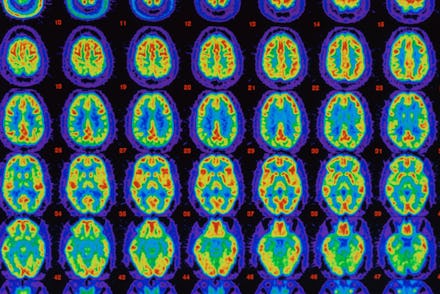

Image Credit: Science